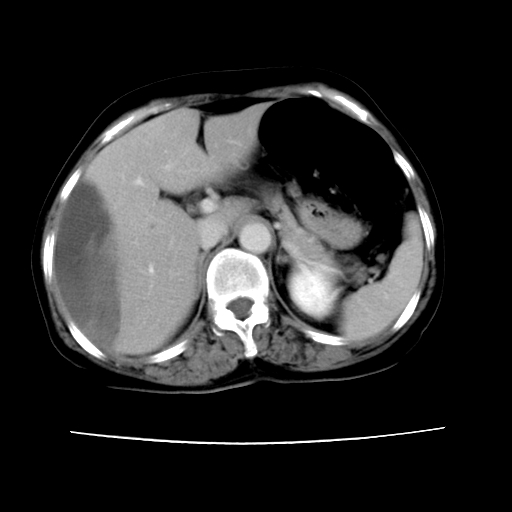

2008-11-10ct平扫(其间去中山医院诊治未行特殊治疗)

2008-11-10ct平扫见并肝内、血膜下血肿基本吸收,肝内低密度灶缩小。此时再做增强ct应有显着意义。对患者/医者都好!

从平扫+增强及治疗后复查片,病变明显缩小,不考虑肝癌出血可能,还是考虑为良性病变可能性大;单纯血肿并包膜下积液吧,病变强化没法解释,肝血管破裂出血吧,增强不符合典型血管瘤的表现,良性肿瘤破裂出血吧,复查片看来好像也不太支持(没做强化也不太好说)。本人还是考虑单纯肝内血肿并包膜下积液,强化是不是血管有外渗。

患者自6月至11月,如果是肝癌,没有经过特殊治疗,想必应该会有所进展吧,而不是ct所见,反而似有病灶减小的趋势。建议增强。

追问病史,患者有过度用力病史,当时立即感腹痛;所以还考虑肝破裂可能性大。